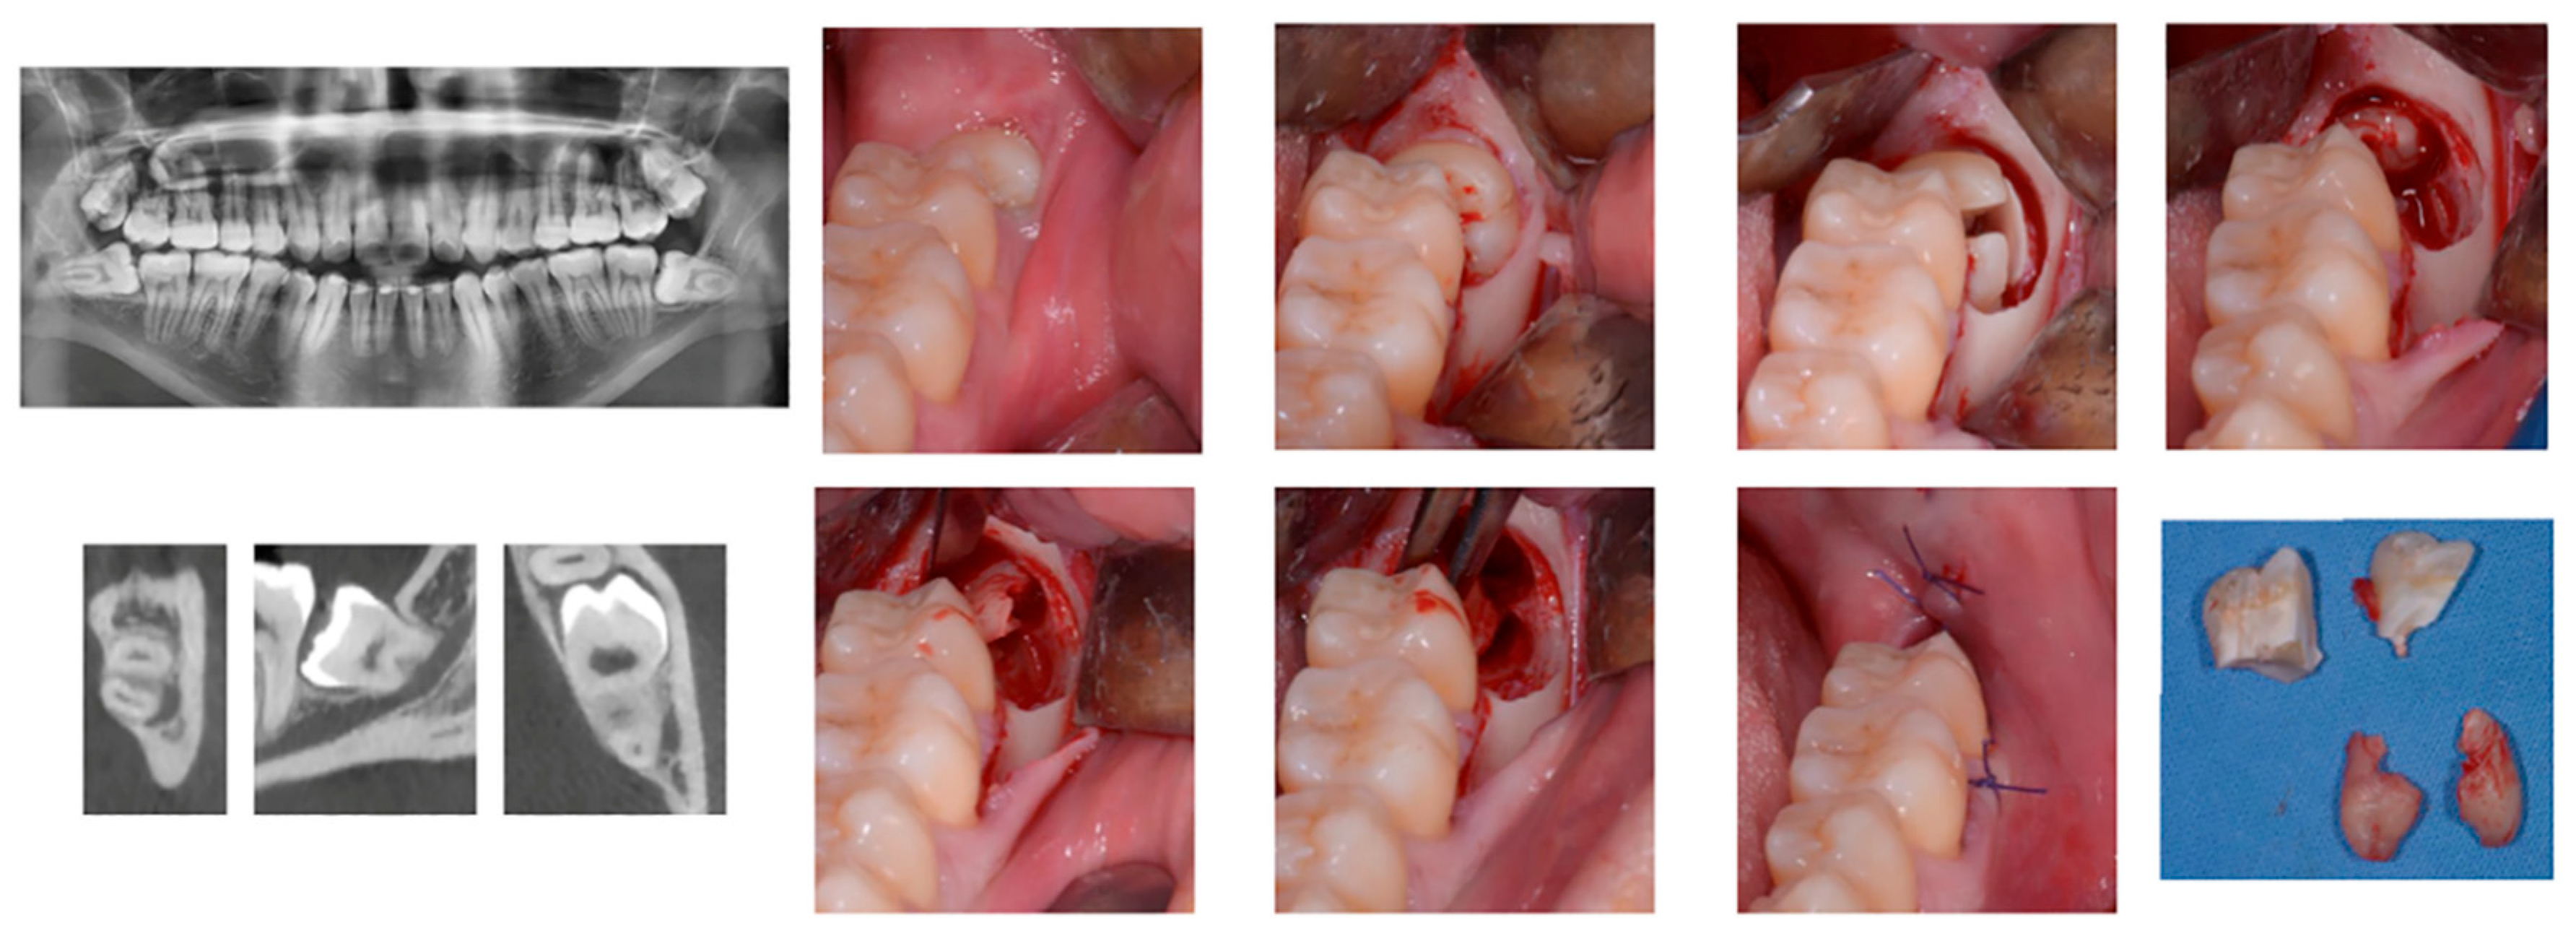

Surgical technique is the same used for extraction of the lower third molar. Patients enrolled in the study will not be exposed to any additional risk than the usual surgery techniques. In Figure 11 a sequence of snapshots from the performed interventions.

Figure 11.

Access to the third molar was performed by a mucoperiosteal flap and a vestibular osteotomy with a fissure burr under continuous irrigation. If necessary, a crown and/or root sectioning was performed using the same fissure burr. After extraction the alveolus was inspected, curetted for granulation tissue removal, and irrigated with sterile saline solution. A 4/0 monofilament nylon suture was used to close the wound without tension. The choice of the third molars was done since their extraction represents a difficult and complex task to be carried out in the rear part of the mouth where large occlusions require, in many cases, the surgeon to keep uncomfortable positions for long periods. Due to the presence of many nerves in the operation zone, high attention must be kept for the whole intervention, increasing the stress and the muscular tightening of the practitioner.